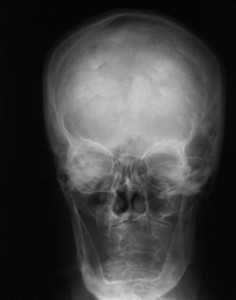

Диагноз ставят на основе жалоб и клинической картины; также используют гистологические методы исследования. На рентгенограмме визуализируется утолщение лобной кости. Синдром Морганьи — Стюарта — Мореля дифференцируют в первую очередь от болезни Иценко — Кушинга и адипозогенитальной дистрофии.

Основным проявлением синдрома М.С.М., без которого он не существует как таковой, является утолщение внутренней пластинки лобной кости (гиперостоз). Это своеобразное разрастание гиперплазированной костной ткани, хорошо распознаваемое рентгенологически и не определяемое при осмотре и пальпации. Явление это довольно распространенное, но в большинстве случаев не проявляется клинически и является рентгенологической находкой [18, 34, 35].

Рентгенологически определяются костные разрастания на поверхности внутренней пластинки лобной кости; они могут быть довольно ограниченными или занимать обширные участки. Иногда они диффузно распространяются на свод черепа, реже - на его основание.

Рентгенограмма черепа (боковая проекция) больного с синдромом Морганьи: резкое утолщение лобной кости (указано стрелкой) за счет гиперостоза внутренней пластинки.

Диагноз устанавливают на основании клин, картины и данных ЭЭГ. Для уточнения диагноза необходимо рентгенол, исследование, т. к. гиперостоз внутренней пластинки лобной кости (рис.), являющийся обязательным признаком этого синдрома, может быть выявлен только при краниографии (см.). О локализации и протяженности изменений судят по снимкам черепа в боковой проекции. Как правило, дополнительные костные разрастания в виде отдельных узлов или разлитого характера располагаются в средней и нижней третях чешуи лобной кости, изредка — и в теменных костях. По сравнению с неизмененными участками кость может быть утолщена в 2—3 раза. Этим изменениям могут сопутствовать различной формы и размеров очаги обызвествления твердой мозговой оболочки в зоне, примыкающей к внутренней поверхности лобной кости.

При длительном течении заболевания и резко выраженном гиперостозе лобной кости из-за уменьшения объема черепа на краниограммах могут быть обнаружены признаки повышения внутричерепного давления (усиление пальцевых вдавлений, углубление борозд синусов и др.).